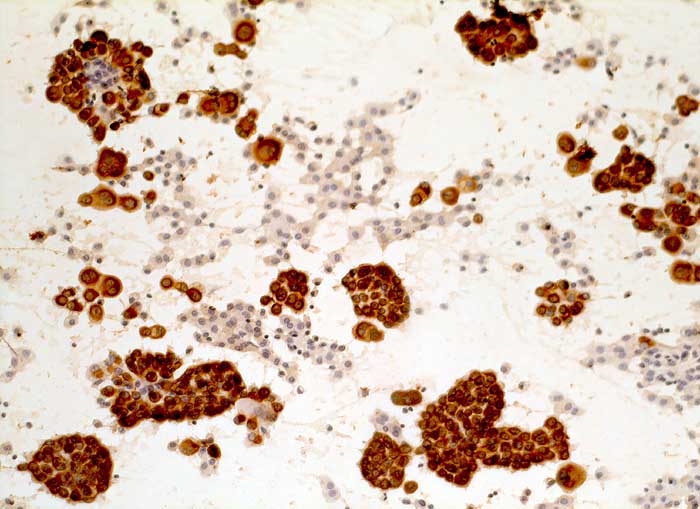

l/ Panzytokeratin (CK22/Lu-5)

Panzytokeratin (CK22/Lu-5)

Anfärbung:

Zytoplasma positiv.

CK22 und Lu-5 repräsentieren Zytokeratingemische, welche einen Grossteil normaler und neoplastischer Epithelzellen anfärben.

Reaktion in Neoplasien:

Die meisten Karzinome und vereinzelte Sarkome reagieren positiv mit diesen Panzytokeratinen. CK22 ist etwas sensitiver und spezifischer als Lu-5. Entdifferenzierte oder sarkomatoide Karzinome können die Positivität für Zytokeratine verlieren.